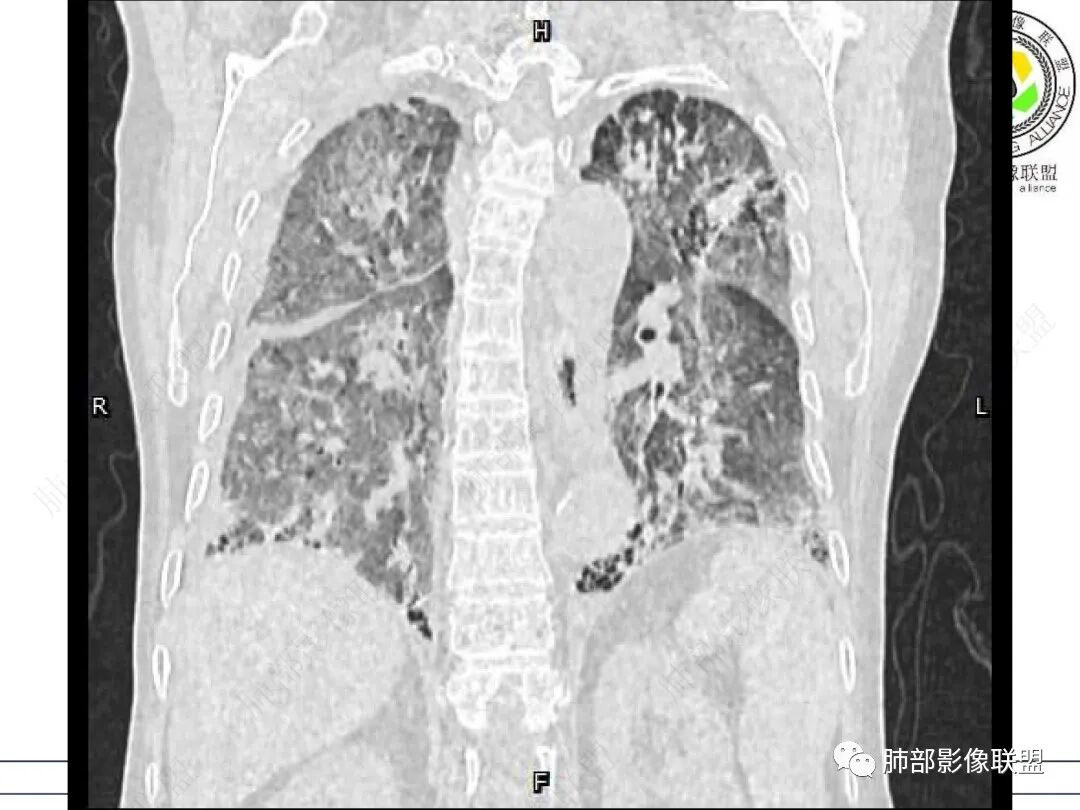

两肺叶后肋膈角区见多发蜂窝状结构破坏表现,双肺叶小叶间隔增厚,左肺上叶后段及舌段和右肺中叶胸膜炎性肉芽肿特点,双侧胸腔少量积液,有类风湿性关节炎治疗史,结缔组织相关性间质性肺病。

发热,有类风湿性关节炎、糖尿病基础病,长期口服激素及免疫抑制剂,双肺多发磨玻璃影及小叶间隔增厚,蜂窝影,支气管扩张考虑非特异性间质性肺炎存在,左肺上叶不规则结节影,周围长毛刺局部肺气肿,考虑慢性炎症,结合pct及crp升高考虑细菌感染,另真菌g升高考虑结合宿主因素,真菌感染需要积极排除。

老年,外阴溃疡加发热,感染指标明显有异常,血气分析,过度呼吸及低氧血症,宿主因素,糖尿病和激素,基础疾病RA。影像,双下肺体积有缩小,有蜂窝?双肺磨玻璃,多发结节,双侧胸水。树芽不明确。是否有旧片,这个患者有UIP背景,是否感染或者UIP急性加重,或者基础上合并肺栓塞及肺水肿?长期激素,没有提供CD4细胞亚群,存在2种情况,1,风湿病没有压制住,肺考虑CTD相关性间质改变,压制过猛,结合感染指标,奴卡是有可能的。激素加糖尿病,结核也带排,激素加磨玻璃加G实验阳性,PCP也带排,临床信息太少,进一步排查

老年女性,有高血压糖尿病及类风湿性关节炎病史,发病前发烧。影像学两肺弥漫性磨玻璃影及斑片影,有渗出性病变亦有间质性改变,支气管血管束增粗,有牵拉扭曲有小气管扩张及间质增厚,两肺下叶胸膜下少许蜂蜜状影。两侧胸腔积液。考虑类风湿性关节炎肺内浸润?合并真菌感染?

老年女性,类风湿关节炎病史多年。发热。以两肺下叶为主弥漫磨玻璃及网格状透亮影,透亮度减低,局部小蜂窝状改变;两肺胸膜下散在几枚实性病灶;双侧胸腔积液。考虑RA-ILDNSIP

两下肺多发蜂窝状表现,双肺小叶间隔增厚,双肺磨玻璃影及部分炎性肉芽肿表现,双侧胸腔积液,有类风湿性关节炎治疗史,结缔组织相关性间质性肺病。患者C反应蛋白和降钙素原都高,是否合并细菌感染

双肺下叶多发蜂窝影,双肺小叶间隔增厚,双肺磨玻璃影,双侧胸腔积液,有类风湿性关节炎,考虑结缔组织相关性间质性肺病,合并感染

①影像表现复杂:较弥漫间质性改变,对称磨玻璃密度为主,小叶间隔增厚,有一定重力分布趋势,未见明显纤维化,气囊及蜂窝位于肺边缘,未见典型“月弓征”。心脏影增大,双侧胸腔积液。

这即可见于间质性肺病,也可见于真菌感染(如PJP)、病毒感染,类风湿,以及肺水肿等等。

一般而言,如存在磨玻璃密度影浑浊,有重力分布趋势,肺表面蜂窝影,胸腔积液等等,并不常见于单纯PJP,除非其他因素叠加。